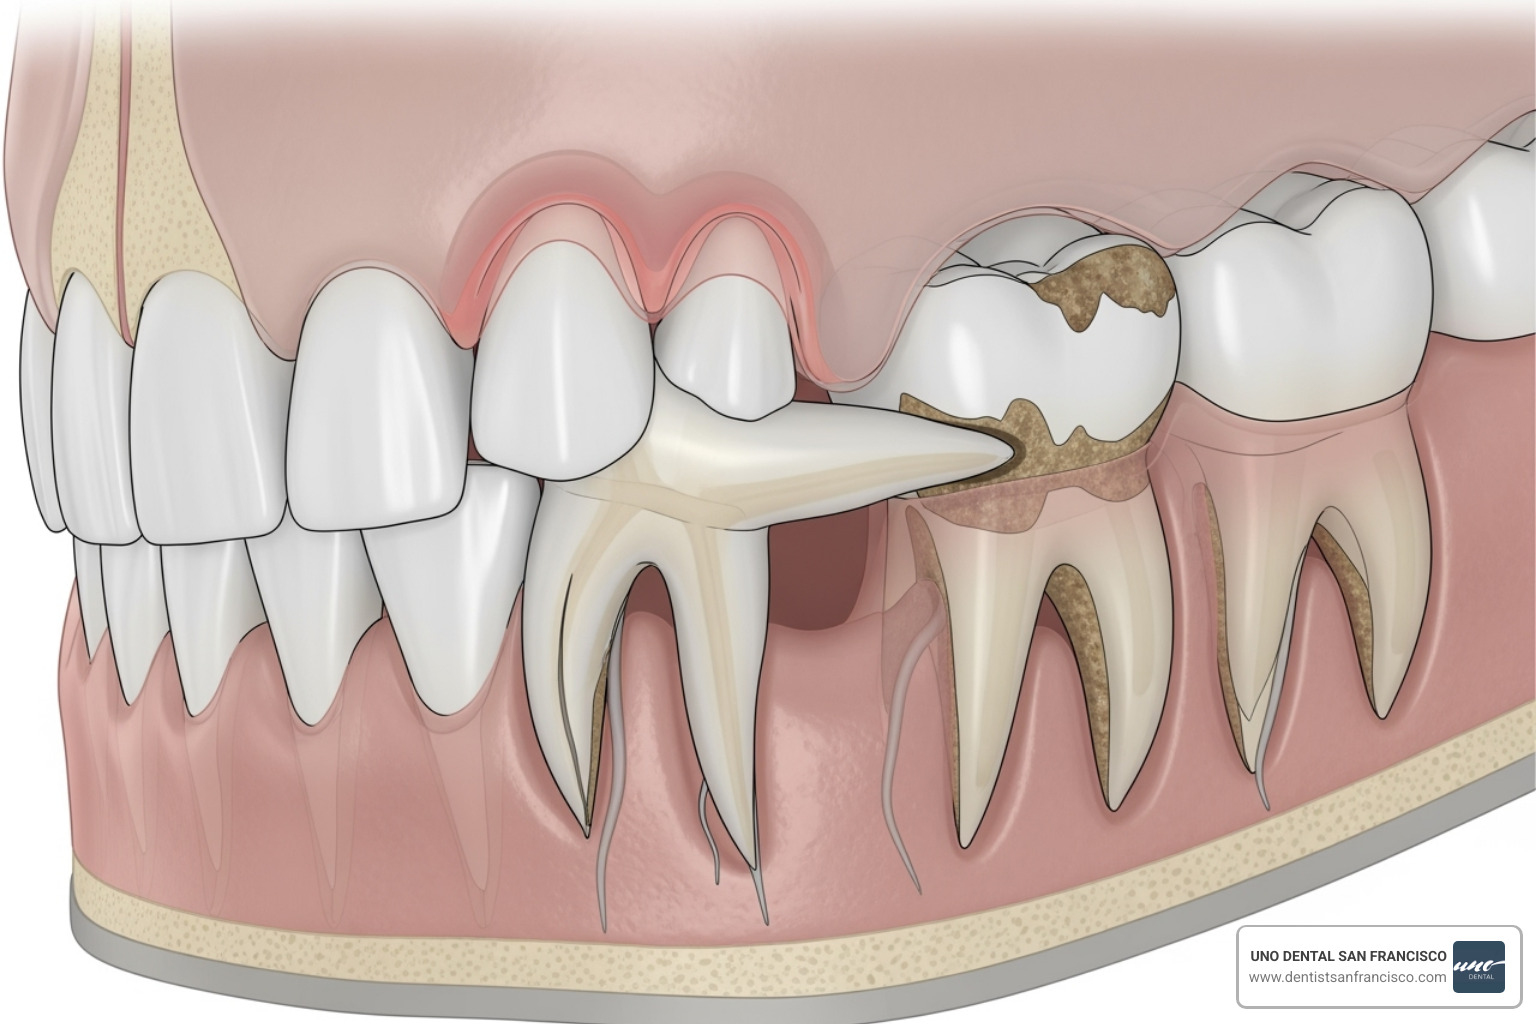

- Damage to Adjacent Teeth: An impacted tooth can push against the next molar, causing root damage, decay, or even tooth loss. This may lead to needing a root canal or crown, which costs more than the initial extraction.

While removing more teeth increases the cost, the primary driver is the complexity of each tooth. An impacted tooth—one trapped beneath the gum or in the jawbone—is more difficult to remove.

- Tooth Position and Angle: A tooth growing sideways or at a severe angle requires more intricate surgical work.

- Root Shape: Curved, hooked, or multiple roots can make extraction more challenging.